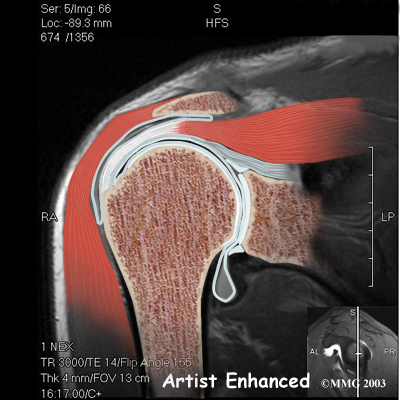

The rotator cuff connects the humerus to the scapula. The rotator cuff is formed by the tendons of four muscles: the supraspinatus, infraspinatus, teres minor, and subscapularis.

Rotator Cuff

Tendons attach muscles to bones. Muscles move the bones by pulling on the tendons. The rotator cuff helps raise and rotate the arm.

As the arm is raised, the rotator cuff also keeps the humerus tightly in the socket of the scapula, the glenoid. The upper part of the scapula that makes up the roof of the shoulder is called the acromion.

A bursa is located between the acromion and the rotator cuff tendons. A bursa is a lubricated sac of tissue that cuts down on the friction between two moving parts. Bursae are located all over the body where tissues must rub against each other. In this case, the bursa protects the acromion and the rotator cuff from grinding against each other.

Bursa